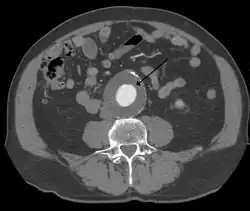

The diagnosis of an abdominal aortic aneurysm can be confirmed by the use of ultrasound. Rupture may be indicated by the presence of free fluid in the abdomen. A contrast-enhanced abdominal CT scan is the best test to diagnose an AAA and guide treatment options.[14]

A large, rapidly expanding, or symptomatic aneurysm should be repaired, as it has a greater chance of rupture. Slowly expanding aortic aneurysms may be followed by routine diagnostic testing (i.e., CT scan or ultrasound imaging).